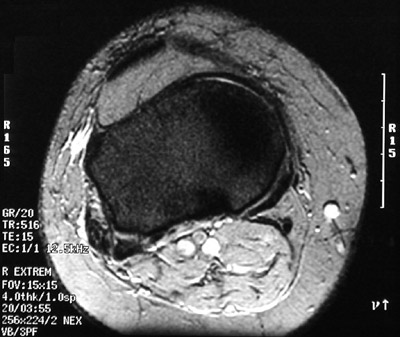

This is a normal axial MRI scan demonstrating the Patellar ligament and Infrapatellar fat pad and Tibial plateau and Subcutaneum and Sartorius and Great saphenous vein and Semitendinosus tendon and Small saphenous vein and Popliteal vessels and Gastrocnemius, medial head and Gastrocnemius, lateral head and Plantaris and Popliteus and Biceps femoris tendon and Iliotibial tract.